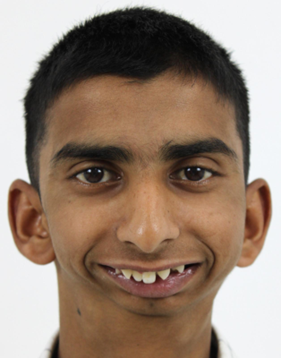

Let us take you through the journey of this young 18 year old boy who had come to us with a complaint of reduced mouth opening and a very short lower jaw. He has had this condition since childhood and has difficulty in eating food and talking and more sadly, has been a victim of bullying at school along with the other functional difficulties mentioned before.

However, in our case represented here, this patient gave us a history of trauma while playing in childhood where he fell from a tree directly on his face. This blunt, direct trauma to the joint caused its enlargement and fusion to the skull. This in turn led to the restricted mouth opening. Trauma to the joint is the most common reason for temporomandibular joint ankylosis. The other causes include spread of infection from the ear, inflammatory diseases, chronic inflammation and developmental conditions.

As the patient was in his teenage years, having completed most of his growth and having a severely deformed lower jaw, a temporomandibular joint reconstruction (TJR) with patient specific implants was planned for him on both sides.

Below are the post-operative photos of the patient on the 8th day post surgery, with the surgical scars noted in the preauricular and perimandibular regions. A marked improvement in his mouth opening from literally one finger mouth opening to around 30mm post surgery was achieved. Along with this, a drastic improvement in his profile is seen.